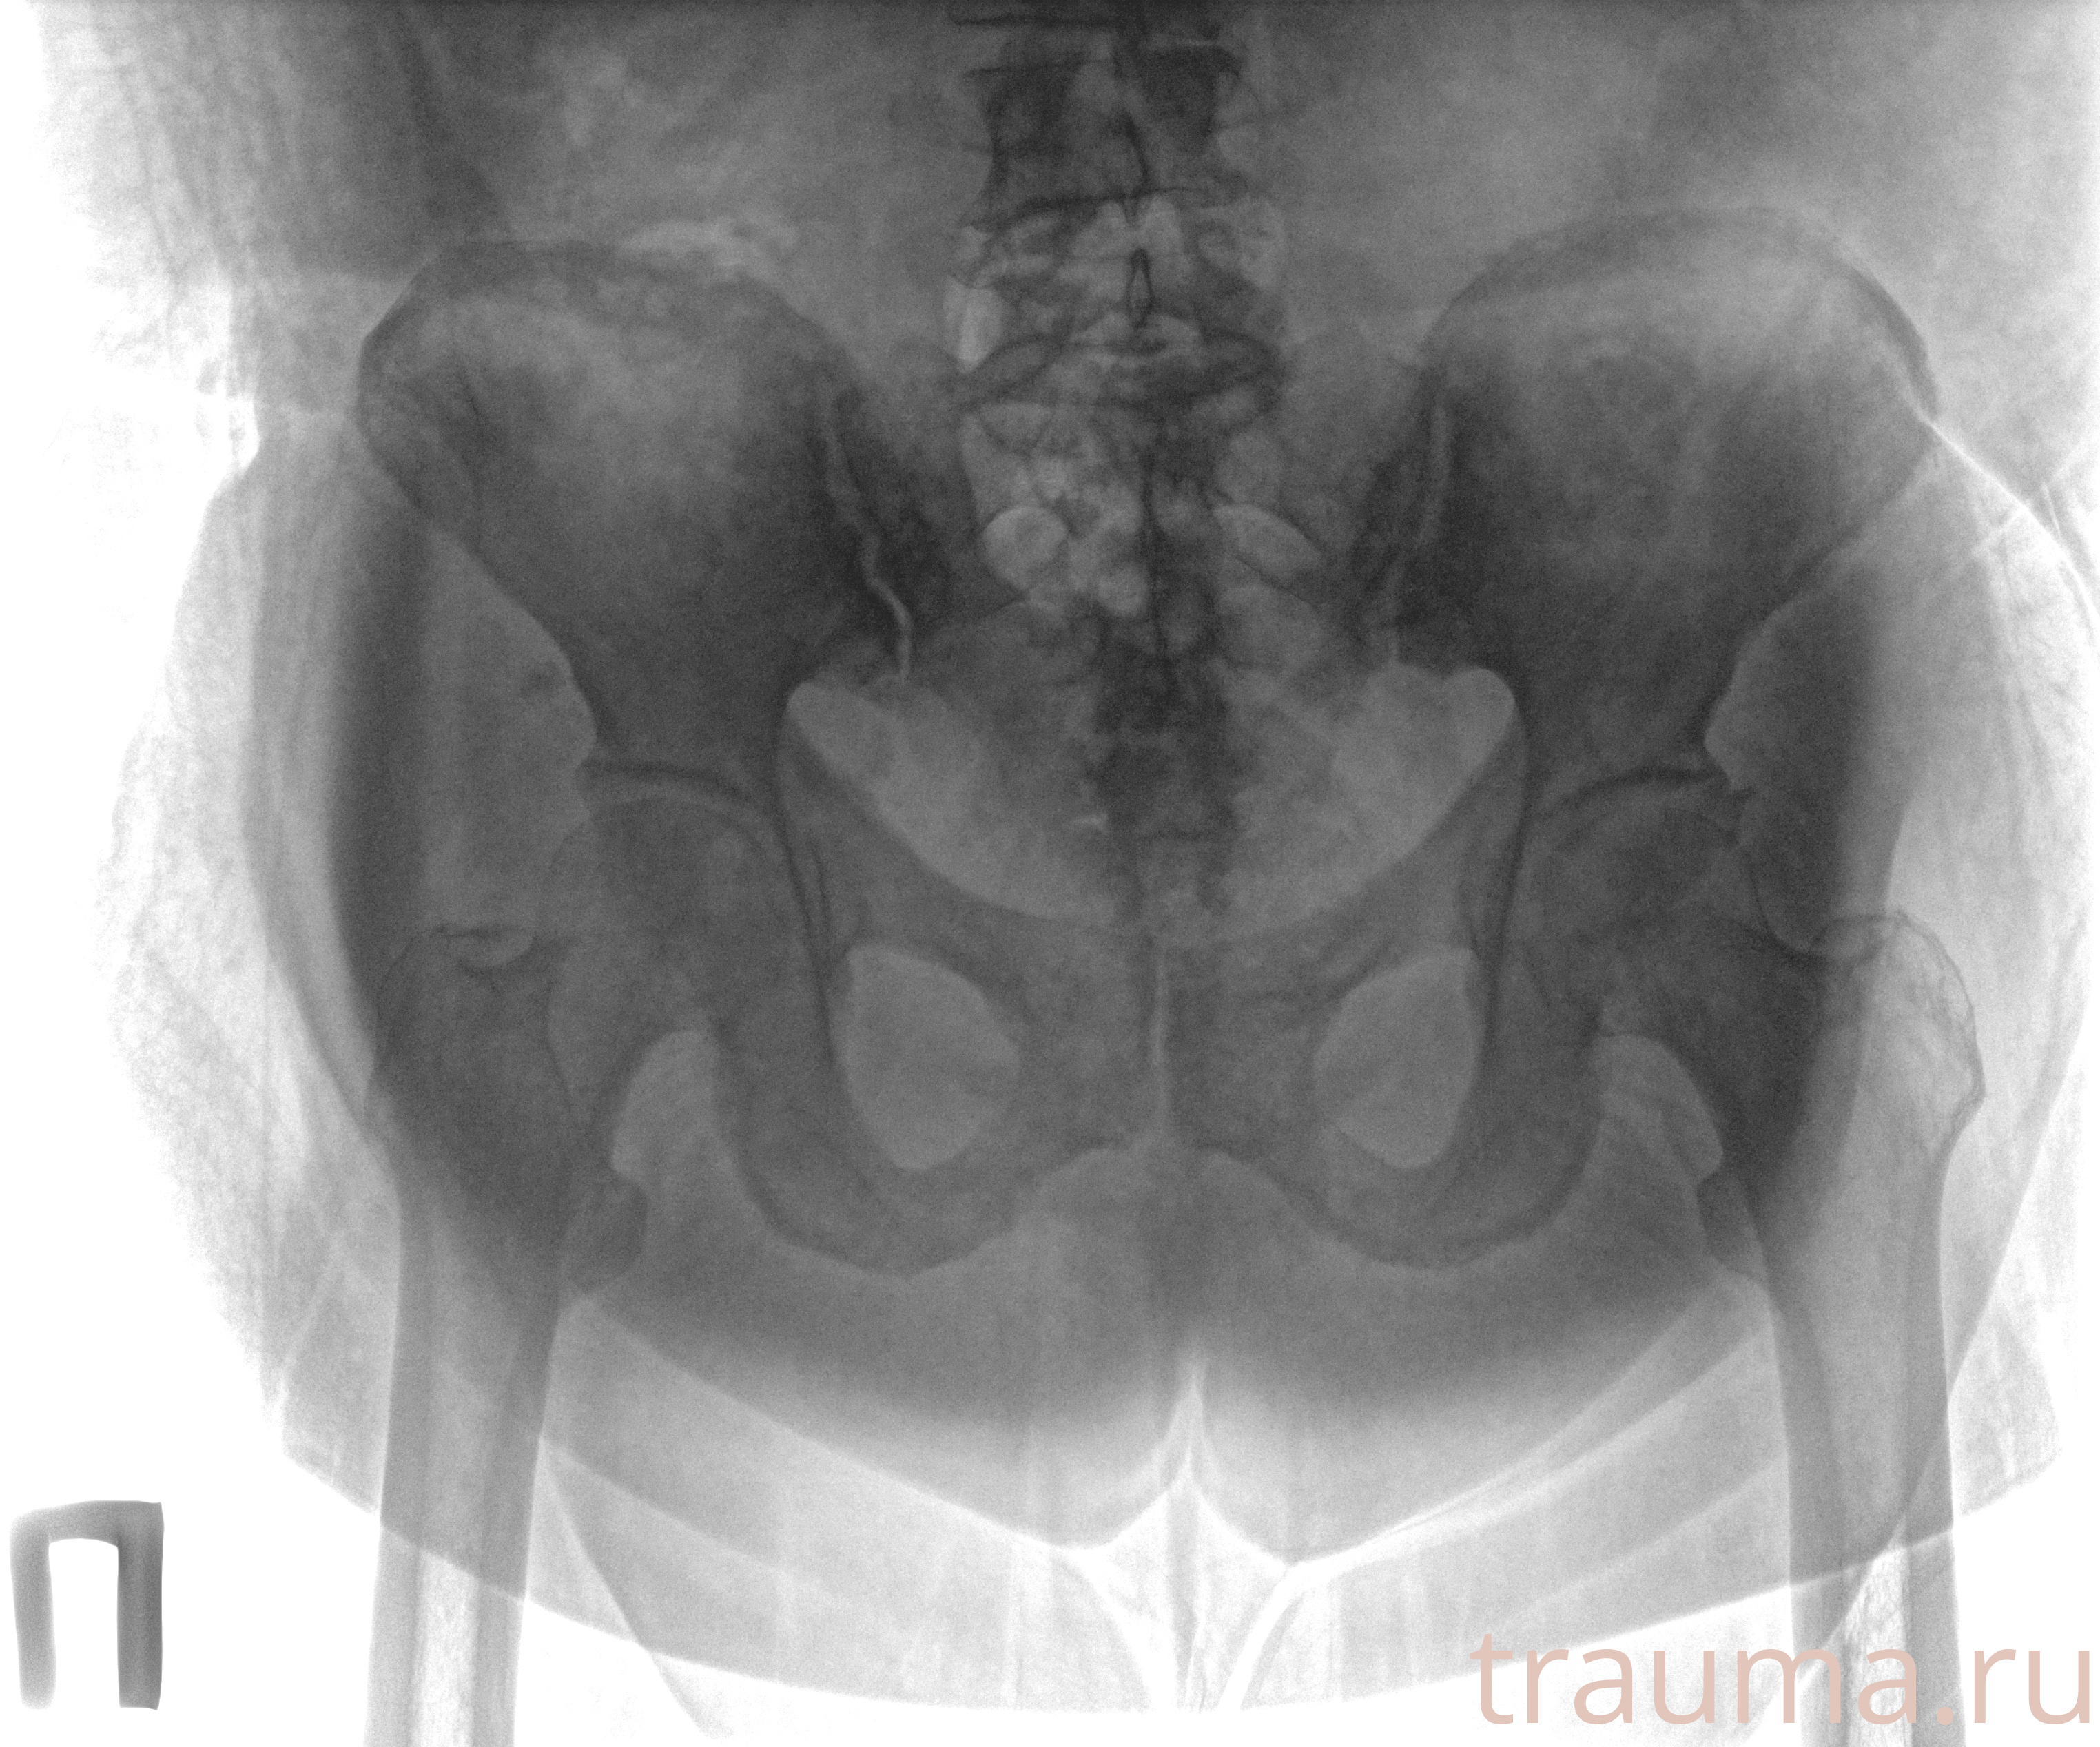

Рентгенограммы

Рентген на дому: по вашему адресу приезжает врач-рентгенолог, травматолог-ортопед с мобильным рентгеновским аппаратом, проводит диагностику травмы или заболевания, делает необходимые рентгенограммы, дает рекомендации по дальнейшему лечению. Получить качественные снимки в домашних условиях возможно благодаря уникальной методике, разработанной МосРентген Центром для института  Склифосовского